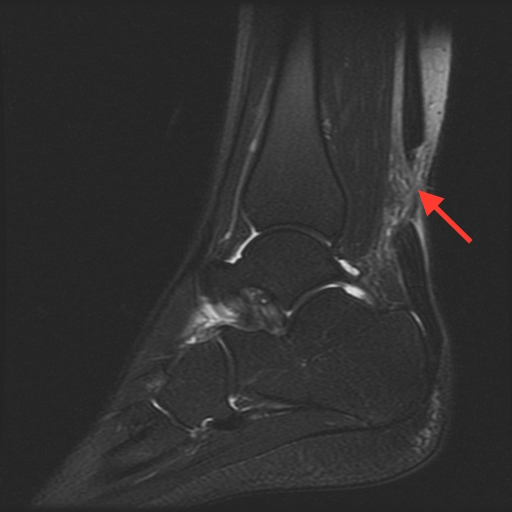

Complete calcaneous (Achilles) tendon laceration, with 2.5 cm separation as noted by red arrow.As an outpatient, the patient went on to have an MRI which confirmed the Achilles tendon was completely severed. The patient went on to have an operative repair of the tendon one week later, with a good prognosis for a normal functional outcome.